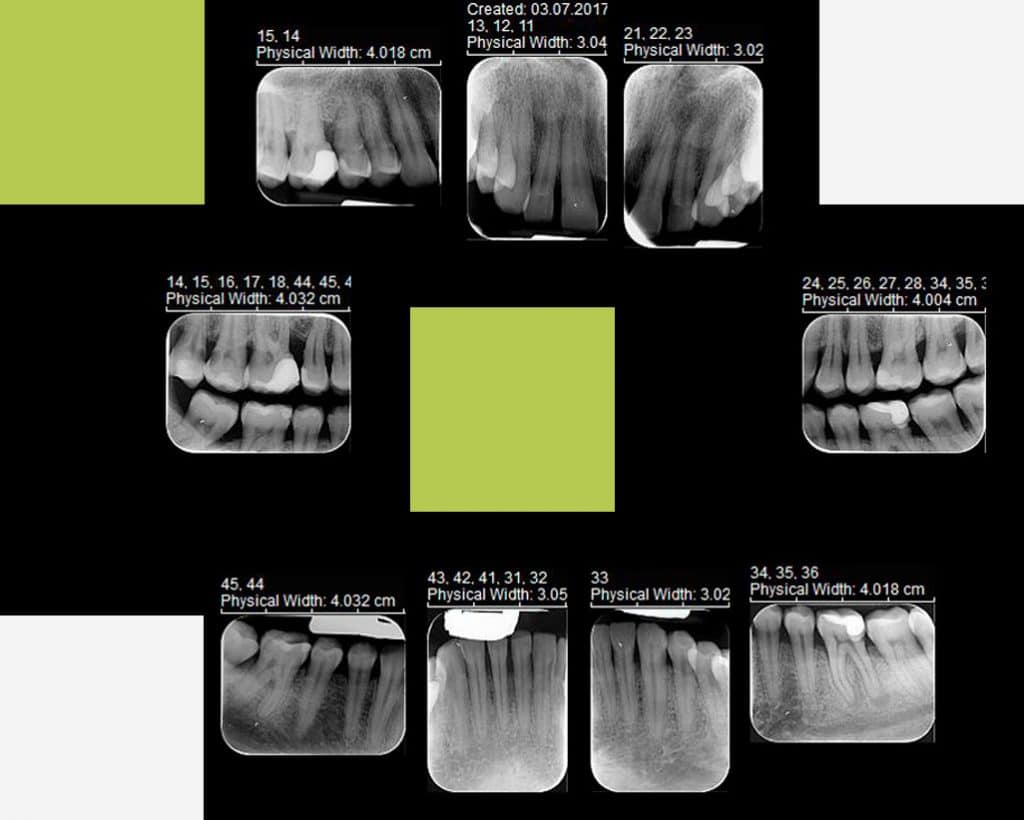

4. Status bi-maxilar

Radiografiile de status bi-maxilar se efectuează pe fiecare zona în parte, cuprinzând întreagă cavitate bucală. Imaginile sunt detaliate pe grupe de dinți în incidente retroalveolare și bite-wing.